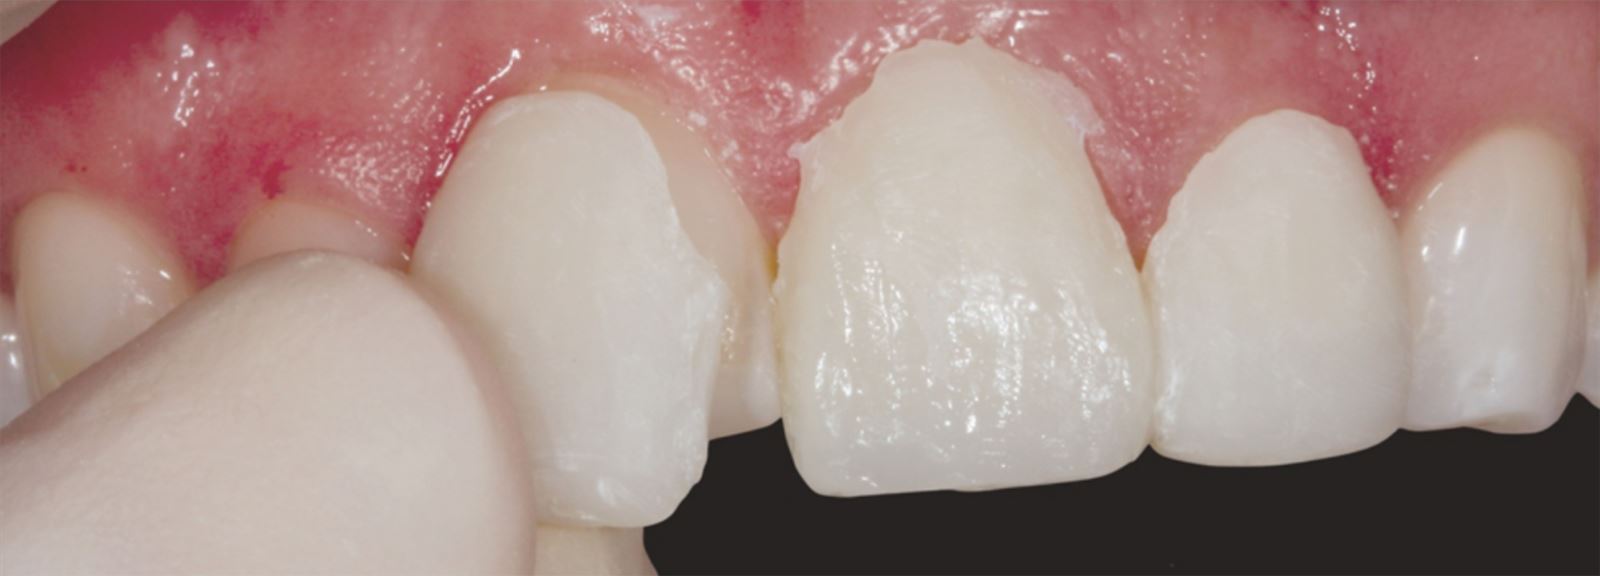

Mladá žena vo veku okolo 20 rokov, ktorú trápila diskolorácia horných frontálnych zubov po skoršej traume, vyhľadala ošetrenie u Dr. Jaleeny Fischer-Jessop, DDS, MBA. Hľadala riešenie, ktoré by obnovilo jej úsmev. Pacientka bola ošetrená konzervatívnou a cenovo dostupnou metódou: kompozitnými fazetami bez preparácie, priamym bondingom. Dr. Fischer-Jessop zvolila tento postup na prekrytie diskolorácie a zjednotenia horných zubov s dolnými frontálnymi – bez nutnosti invazívnejších výkonov, ako sú implantáty, alebo nákladných laboratórne zhotovovaných faziet. Na zosvetlenie zubov boli vybrané odtiene B1D a Enamel White (EW) a odtieň Universal Body (UB) kompozitu Transcend™ bol použitý na prirodzené splynutie okraja v cervikálnych oblastiach.

Pacientka v 20 rokoch s anamnézou traumy horných frontálnych zubov. Napriek tomu, že trauma prebehla, zuby zostali stabilné, takže implantáty neboli nutné.

Pacientka mala výrazné estetické obavy a súčasne bola finančne limitovaná. S ohľadom na tieto okolnosti boli zvolené kompozitné fazety bez preparácie ako vhodné riešenie.